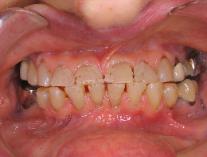

Pre-op

Patient's new smile

Temporary

Finished Crowns

Patients often ask how they will look

with temporaries during treatment.  We

do our best to make temporaries that

not only protect the teeth and look

natural, but also serve as a preview of

our final restoration.

We use our temporaries to determine

whether our final crowns should be

longer, shorter, lighter, darker for the

best final result that we can achieve.